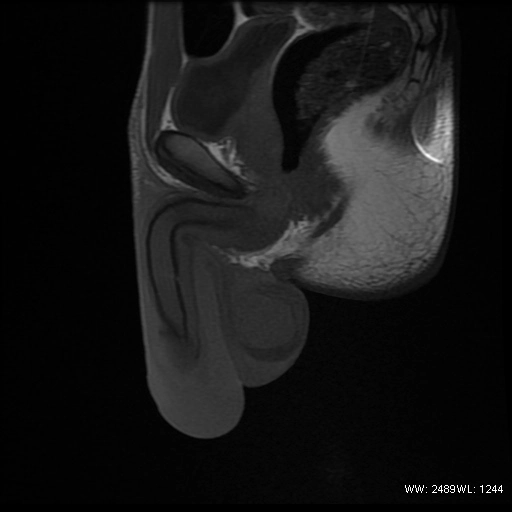

Chấn thương niệu đạo (Urethral injury)

Gãy dương vật (Penile fracture)

Bệnh Peyronie (xơ chai dương vật)